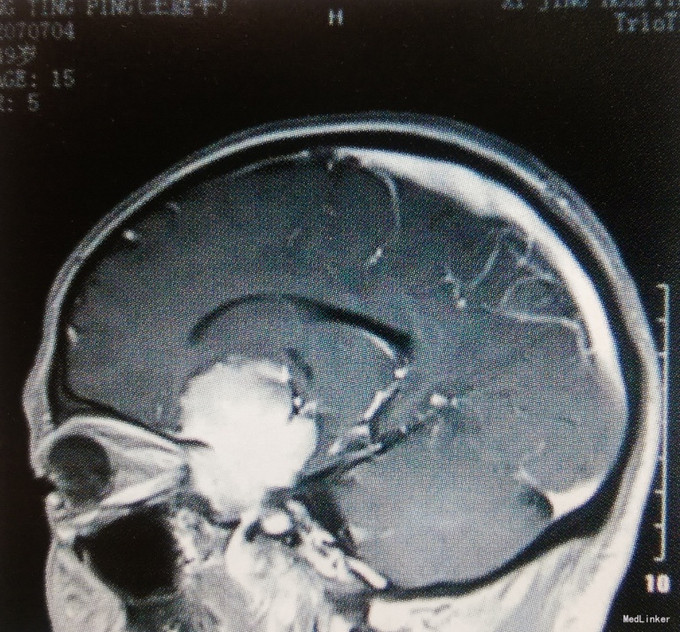

患者,男,49岁。主因头痛伴视力下降半年入院。 患者于半年前无明显诱因出现间断性头痛,钝痛,左侧额颞部为甚,同时伴左眼视物模糊。头颅MRI检查:左侧鞍旁见一类圆形病变,大小约5.7cmх4.1cmх4.6cm,边界清楚,三脑室前部受压变形,增强扫描明显均匀强化,考虑为脑膜瘤。发病以来,精神、饮食差,大小便正常,恶心、呕吐严重,无抽搐、昏迷。体重无明显变化。

查体:体温36.9℃,脉搏78次/分,呼吸20次/分,血压130/80mmHg。意识清楚,双侧瞳孔等大同圆,直径约3.0mm,直接、间接对光反射均灵敏,右眼视力为0.8,左眼视力仅有光感;四肢肌力、肌张力正常,余神经系统查体无明显异常。 术前影像学检查颅脑MRI:左侧鞍旁见一类圆形病变,大小约5.7cm×4.1cm×4.6cm,边界清楚,三脑室前部受压变形,增强扫描明显均匀强化,考虑为脑膜瘤。